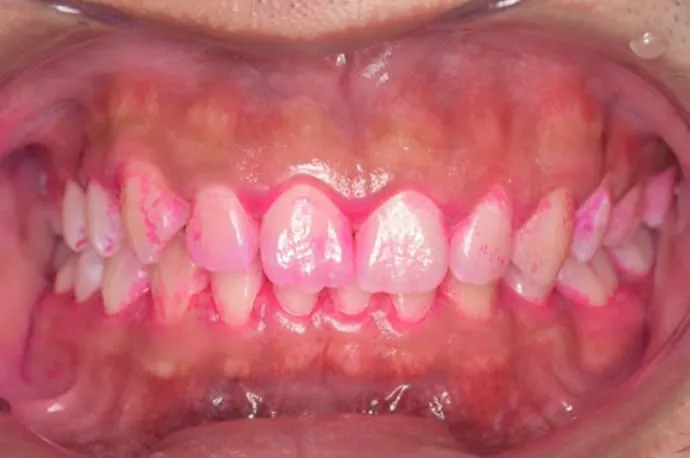

歯磨き指導例

治療前

治療後

こちらの画像は、ブラッシング前後の染め出しの画像です。汚れがついている部位は濃くピンクに染まります。1回の歯磨き指導でも、汚れの付着が大きく減っていることが確認できます。ぜひ一度、高輪の歯医者「TAKANAWA GATEWAY Clinics 歯科・矯正歯科」へご来院いただき、自己流の歯磨きから卒業してみませんか?